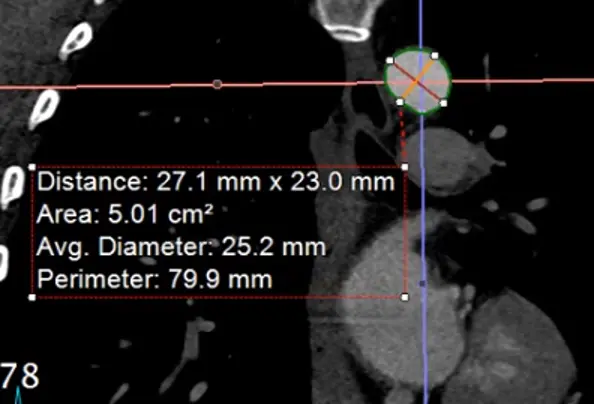

Measure aorta using âcandy caneâ view

- Rotate your cross hairs so you are cutting through both the ascending and descending thoracic aorta.

- Last step is to click the

MPRbutton at the top right and change it toMIP - Hit

Ctrl, hit the button down and drag sideways, you can increase/decrease the slab thickness. For example, this may allow you to capture the entire thickness of the aorta in different planes by manipulating the slab thickness. - Hit

Dto make measurements at different levels of the aorta. Provides a sanity check to make sure you didnât miss a larger/wider part of the aorta. - Right-click and select âCaptureâ to store this image with your measurements.